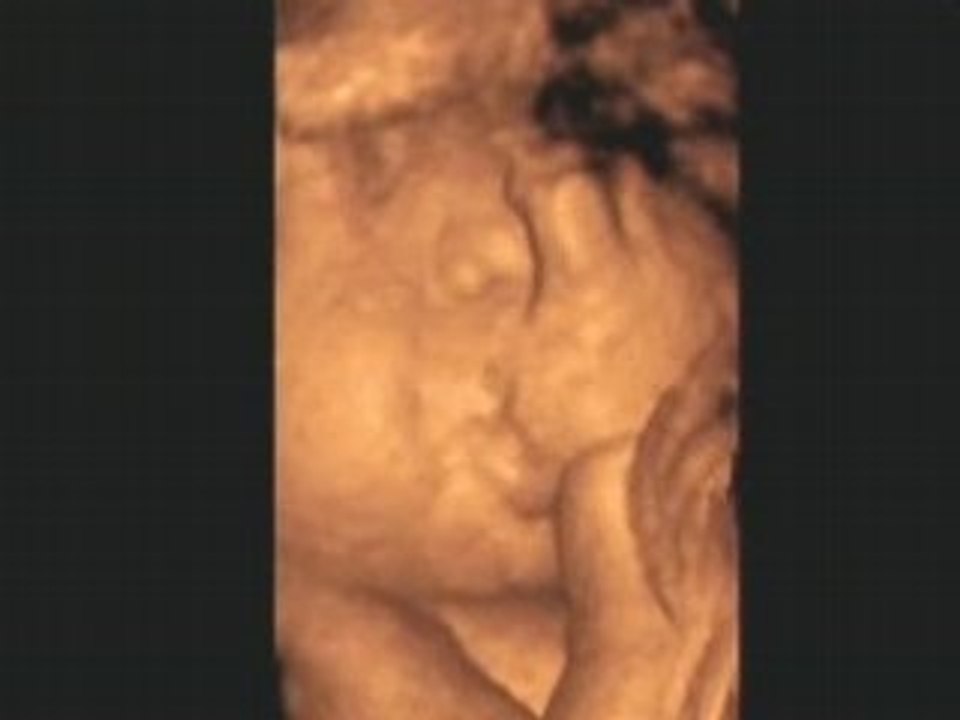

A quoi ressemble la vie et le monde à travers les yeux d'un bébé? Diffusée sur Arte ce samedi 23 octobre, la série H24 a réuni plus de cent femmes à travers le monde pour créer 24 épisodes manifestes qui rendent compte des violences qu'elles subissent au quotidien Le dernier né de MarieMonique Robin (Le monde selon Monsanto) vient d'être diffusé sur Arte "Né" car il s'agit bien là de naissance naissance d'un nouveau monde vers lequel il va bien falloir transiter pour notre (sur)vie, et la fin d'un autre et c'est pas trop tôt "Nous en savons assez sur l'avenir